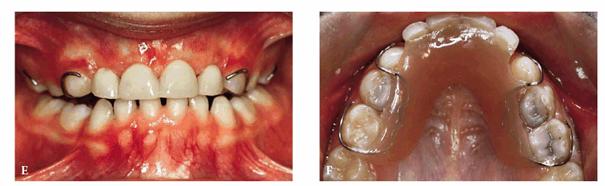

A female patient, 6 years, 7 months old.

PROBLEM: The patient's frontal view showed a serious bimaxillary

crowding with deviation of the midline. When teeth #7 and #10 erupted, crowding

problems greatly increased. Also, tooth #10 was in crossbite (Figure 27-9A).

Figure 27-9A: A serious bimaxillary crowding with deviation of the midline in a 6-year, 7-month-old female.

TREATMENT: After a

short observation period, while the lateral incisors erupted, the pediatric

dentist and the orthodontist initiated therapy. M and R were sliced, and a lip

bumper was applied to K and T. The occlusal surface rose to resolve the

crossbite of the upper left lateral incisor. The maxillary arch was treated orthodontically

to correct the alignment (Figure 27-9B).

Figure 27-9B: After a short observation period, the early orthodontic therapy is started.

RESULT: The patient underwent an early orthodontic treatment for 1 year

that achieved arch balance, improvement of esthetics, and health of the oral

tissues. Furthermore, the improved smile contributed to greater self-confidence

and an improved sense of well-being (Figures 27-9C and D).

Figure 27-9C and D: The patient's smile and the lower arch after the orthodontic treatment: good balance and esthetics are achieved.